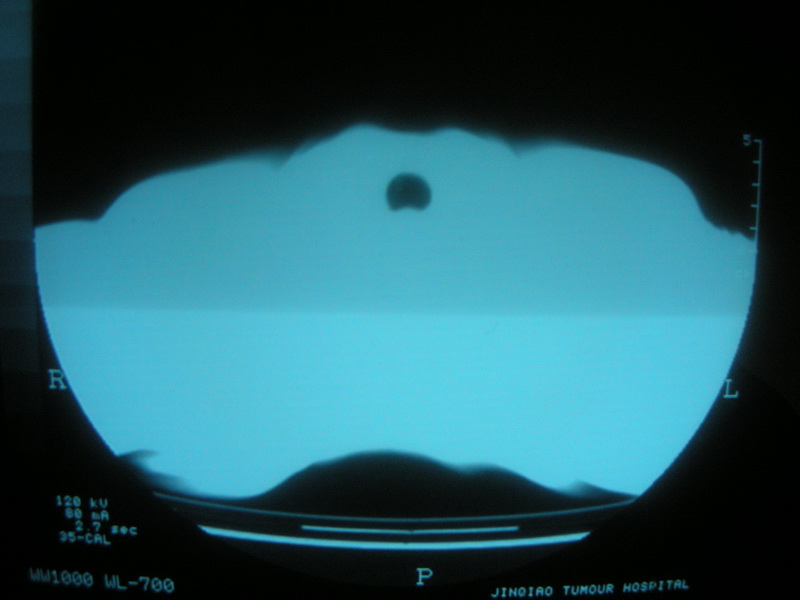

标题: CT11692:男,63岁,糖尿病史15年.抗炎治疗7天,病情 [打印本页]

标题: CT11692:男,63岁,糖尿病史15年.抗炎治疗7天,病情

请老师看看是结核还是炎症?

根据影像表现及临床符合结核感染。

双肺继发性肺结核伴感染!